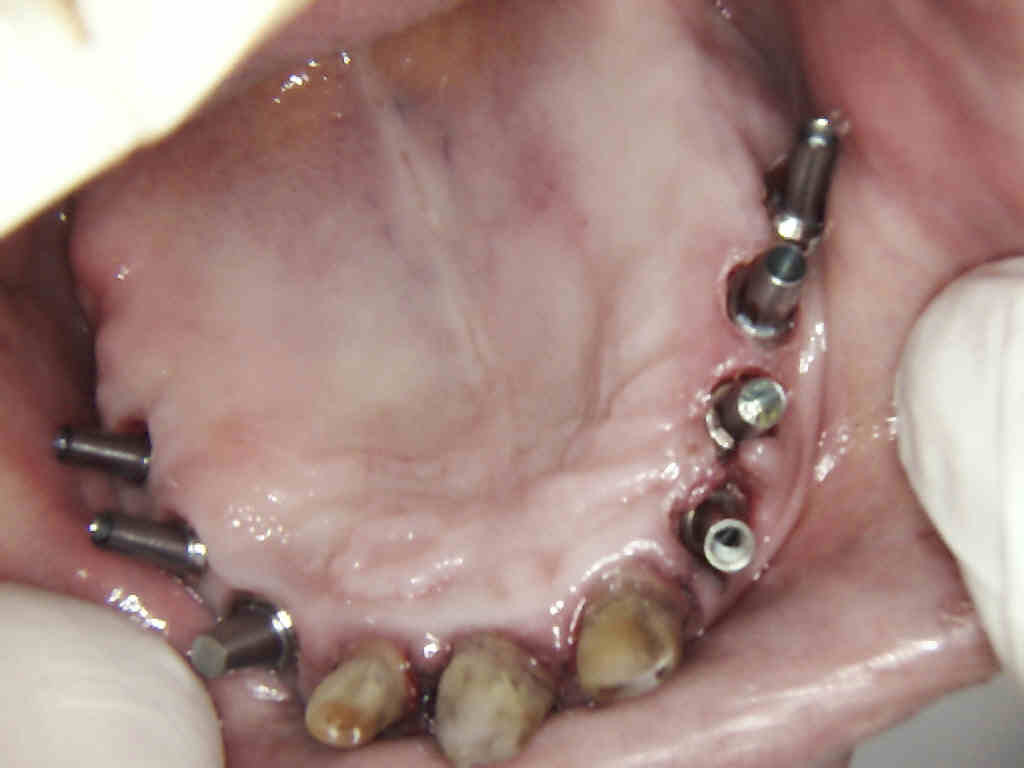

Oftmals kommt es vor, dass ein Zahn durch Karies, Frakturen, ausgedehnte Defekte oder übermäßige Abnutzung so zerstört ist, dass eine Wiederherstellung mit einer Füllung nicht mehr möglich ist.